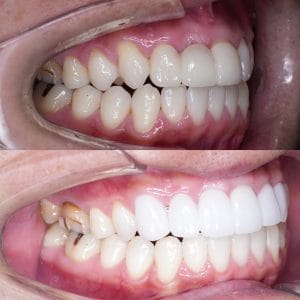

Case025

他院ですでに3本セラミック治療を行っている男性の患者様です。

歯並びと色を変えたいということで当院にお越しくださいました。

・透明感のあるセラミックに変更

・前に出ている歯を内側に入れてスマートな印象に

したことにより、とても洗練された口元になったと思います。

この白い色もとてもお似合いの方で、治した私もセット後に思わず「似合いますね」と言ってしまいました。

当院はセラミック矯正だけではなく、マウスピース矯正、ワイヤー矯正と全ての治療メニューを用意しております。

患者様の主訴と悩み、治療費にかけられる費用と期間をお伺いし、ご要望に合う治療方針をご提案、ご相談しながら決めています。

この方の場合は

・既に歯を3本削られている

・前医で入れた大きなセラミックは矯正しても小さくはならない

・色を変えたい

以上の理由でセラミック矯正を選んでおります。